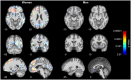

Materials and methods: T1-weighted images from 5,518 women (MAge = 70.20, SD = 3.54; age range: 65-82 years) and 7,595 men (MAge = 70.84, SD = 3.68; age range: 65-82 years) without neurological or psychiatric impairments were included in voxel-based morphometry (VBM) analysis in CAT12 with threshold-free-cluster-enhancement (TFCE) across the whole brain.

Results: We found a significant decrease of GM volume in women in the superior frontal gyri, middle temporal gyri, fusiform gyri, temporal poles, cingulate gyri, precunei, right parahippocampal gyrus and right hippocampus, right ventral diencephalon, and right pre- and postcentral gyrus. Only small effects were found in men in subcallosal area, left basal forebrain and entorhinal area.